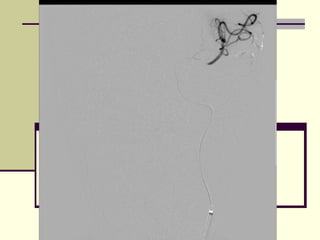

‫‪ MRA‬אנגיוגרפיה -‬

‫חוסר זרימה בעורק ה ‪MCA‬‬    ‫‪‬‬

‫מימין‬

‫רוב ההמיספרה הימנית לא‬   ‫‪‬‬

‫מקבלת דם‬